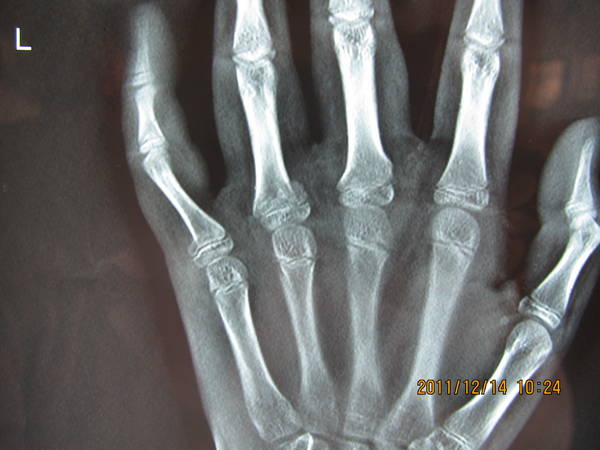

[修复重建] 小儿手指骨骺损伤如何处理

小儿 骨骺损伤

患儿,男性,13岁。

个人认为小指近节基底骨折成角旋转角度需要干预,至于如何干预,请大家讨论。

小指已明显旋转畸形,切开复位克氏针固定应该好一点,一月即可拔出克氏针